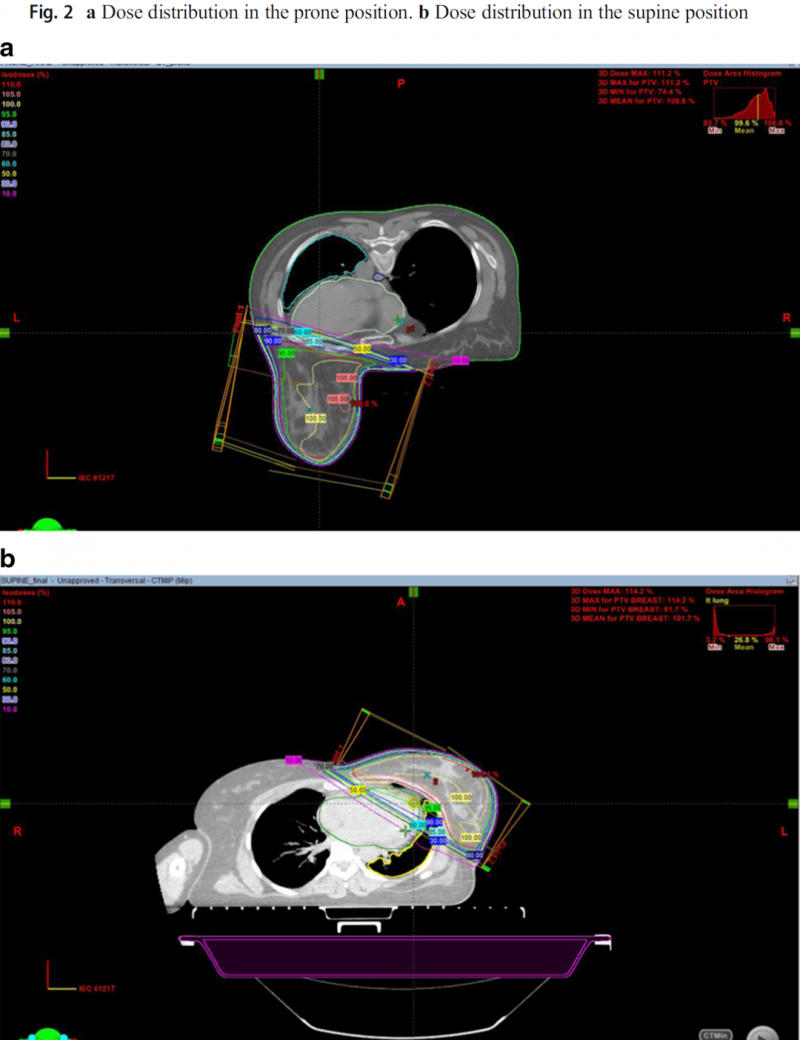

乳腺癌放疗,乳腺癌患者仰卧位与俯卧位放疗技术的剂量学比较 乳腺癌

乳腺癌乳腺癌放疗,乳腺癌患者仰卧位与俯卧位放疗技术的剂量学比较

乳腺癌放疗,乳腺癌患者仰卧位与俯卧位放疗技术的剂量学比较早期乳腺癌患者生存时间更长,因此降低晚期毒性的放射治疗技术是非常重要的。在该研究中,对左侧乳腺癌患者的仰卧位和俯卧位放疗技术进行了剂量学比较。01、研究背景虽然保乳治疗后患者已采用仰卧式乳房照射技术,但也可提倡俯卧式乳房照射,以减少急性和晚期毒性,特别是对于下垂较大的女性。随着CT等影像学技术的不断发展